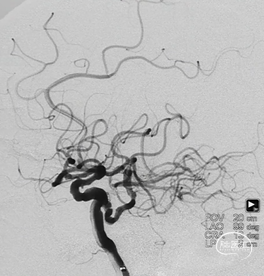

本院造影:

1. L-ICA:永存三叉动脉起始多发斑块伴局部瘤祥突起,左侧大脑后功脉P2段动脉瘤。(图7)

图7

3. L-ICA:永存三叉动脉起始多发斑块伴局部瘤祥突起,左侧大脑后功脉P2段动脉瘤。(图9)

图9